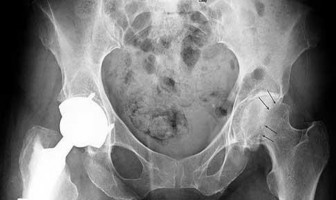

A 22-year-old male is brought to the trauma bay after a motorcycle accident. Pelvic radiographs demonstrate significant widening of the pubic symphysis, indicative of an anteroposterior compression (APC) injury. To classify this as an APC Type III injury (Young-Burgess classification), which of the following combinations of posterior pelvic ring ligaments must be completely disrupted?

Correct Answer: Anterior sacroiliac, posterior sacroiliac, sacrospinous, and sacrotuberous ligaments

Explanation:

In the Young-Burgess classification, APC I involves symphysis widening <2.5 cm with intact posterior ligaments. APC II involves symphysis widening >2.5 cm, disruption of the anterior sacroiliac, sacrospinous, and sacrotuberous ligaments, but the critical posterior sacroiliac (SI) ligaments remain intact (rotationally unstable, vertically stable). APC III indicates complete disruption of the anterior SI, sacrospinous, sacrotuberous, AND the posterior SI ligaments, resulting in a completely unstable hemipelvis (both rotationally and vertically).